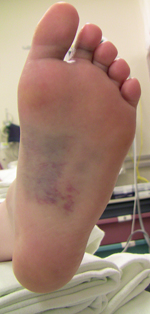

The discoloration on the bottom of the foot is very suggestive of a Lisfranc injury.